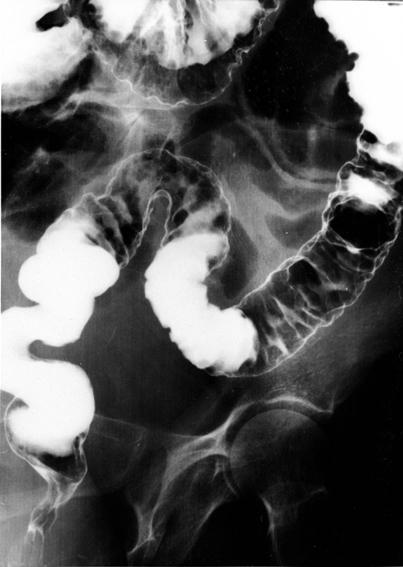

偽膜性腸炎のX線像 注腸二重造影像写真です。下部大腸ひだ腫大がびまん性に腫大、境界が不明瞭な小隆起が無数に認められます。そのため腸管の辺縁も不整になっています。

疾患(病理主体)の分類炎症性・潰瘍性疾患/偽膜性腸炎

部位(臓器別)大腸/2区域以上の大腸にまたがるもの

検査方法X-P

病変の最大径(ミリ)10〜14

多発腫瘍(同一臓器)有(同時性)